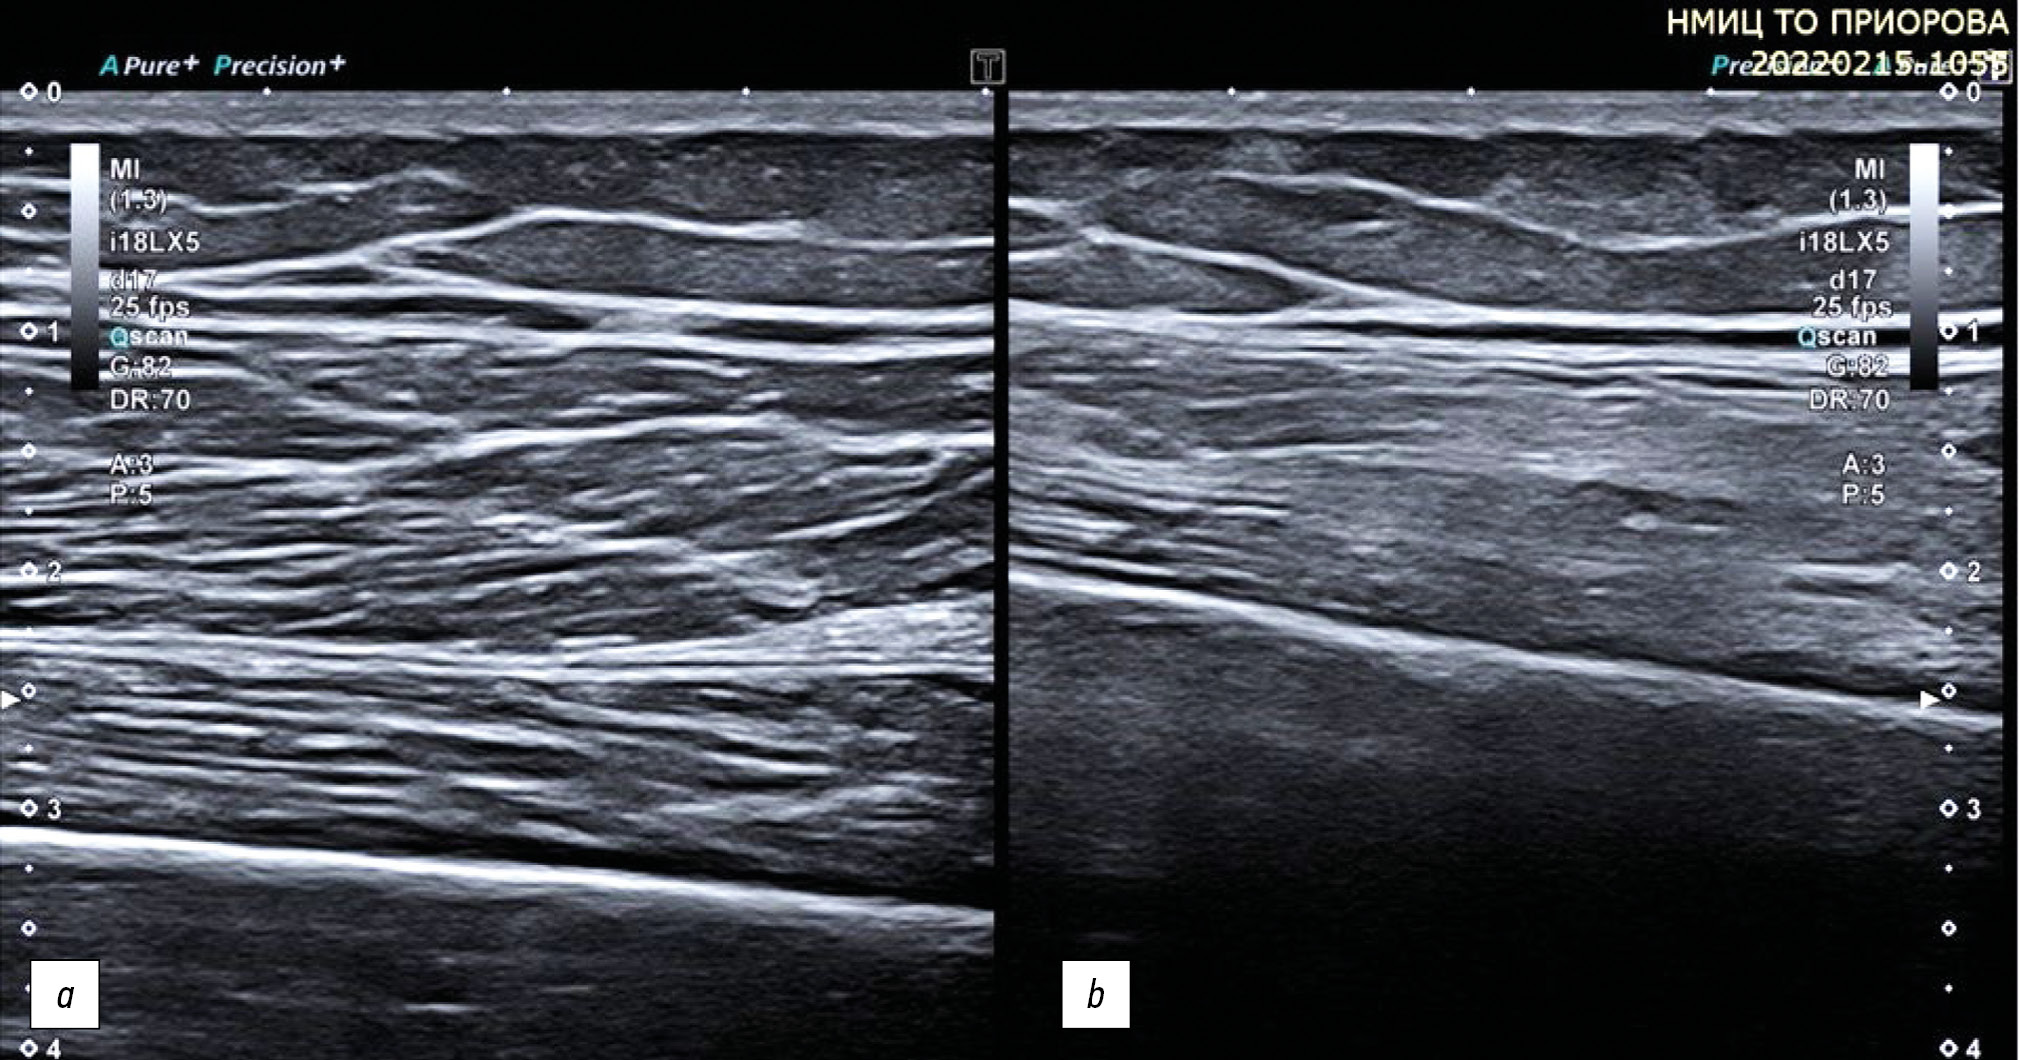

In polyneuropathies, including autoimmune neuropathies, nonspecific changes in the structure of peripheral nerves are also detected; an example is nerve thickening caused by thickening of nerve fibers in the composition of the nerve trunk, and a decrease in echogenicity. At the same time, differentiation into fibers and the clarity of the nerve contours are preserved (Fig. 8).

Fig. 8. Ultrasound examination of the tibial nerve in a patient with disimmune neuropathy illustrating nonspecific changes in the peripheral nerve structure. Transverse (a) and longitudinal (b) projections.